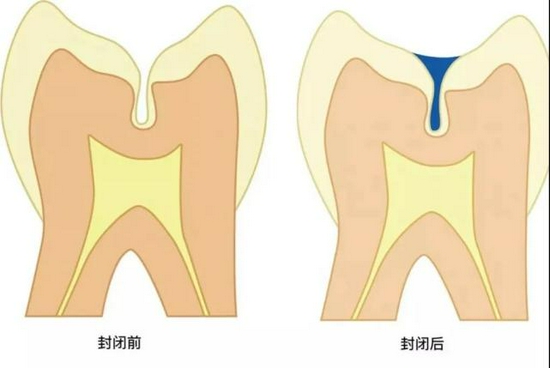

所谓窝沟封闭是指不损伤牙体组织,将窝沟封闭材料涂布于牙冠咬合面、颊舌面的窝沟点隙,当它流入并渗透窝沟后固化变硬,形成一层保护性的屏障,覆盖在窝沟上,能够阻止致龋菌及酸性代谢产物对牙体的侵蚀,以达到预防窝沟龋的方法。

它封闭了较深的窝沟,使咬合面变得光滑,避免了食物残渣在此存留,并使原本不易清洁的牙面变得利于清洁与自洁。

它封闭了致龋菌进入窝沟深处的通道,使窝沟深处釉质较薄,抗龋能力差的缺点得以规避,断绝了窝沟龋发生的途径。